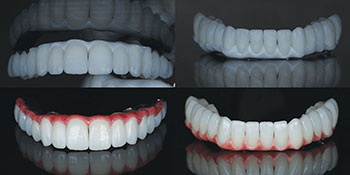

After thorough evaluation, we planned for a FP3 restoration in the maxilla and mandible (implant-supported crowns that mimic natural teeth and allow for flossing) and a fixed prosthesis with pink material to replace tissue contours.

Thanks to close collaboration with LA Dental Implant Lab, we were able to redesign and mill a custom titanium substructure to ensure passivity and a precise fit. We used zirconia thimble supra structure design and individual crowns to allow flossing through embrasures. This fabricated individual, highly aesthetic zirconia crowns, creating a natural-looking, functional and hygienic restoration (Figs. 13–14).

Failure to Load

Final seating: Perfect fit, zero adjustments

Final delivery day could not have gone smoother. No adjustments were needed—a testament to precision planning and execution along with digital workflows. Patient satisfaction was beyond expectations—she could floss between her teeth, enjoy a natural smile and eat comfortably. The occlusion was balanced and aesthetics were on point, and the patient left with tears of joy (Figs. 15–17).